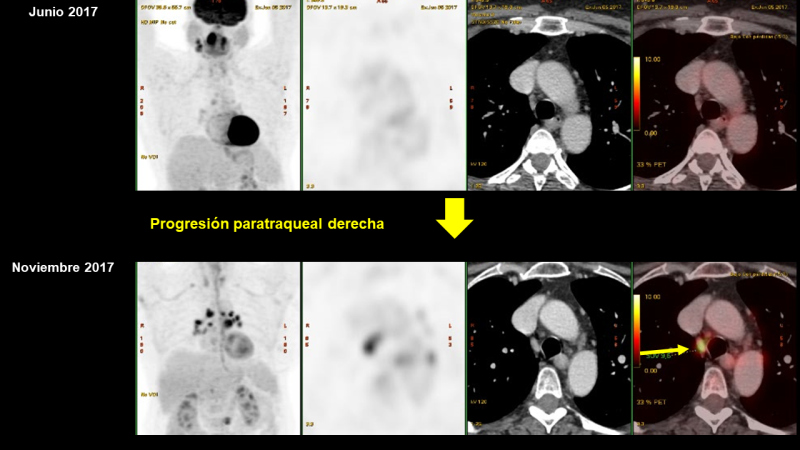

Un estudio PET-CT de re-estadificación muestra (Figs. 3-7):

Progresión de la afectación ganglionar mediastínica, hiliar, retroclavicular derecha y en hilio hepático.